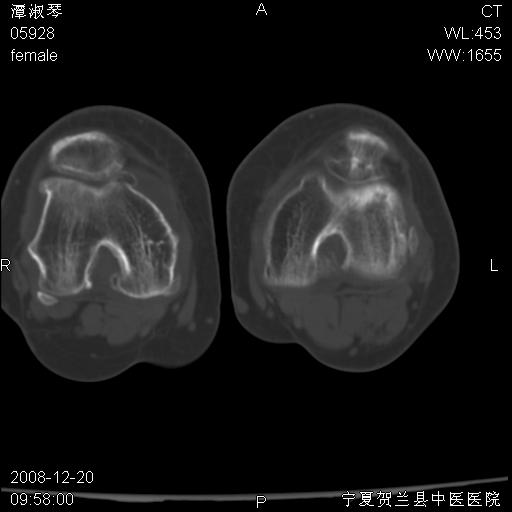

标题: CT17526:请各位看看是啥?

内生软骨瘤?骨梗死?

考虑内生软骨瘤可能性大

考虑-----骨梗死+退变

支持骨梗死,退行性骨关节病,膝关节积液.

考虑骨梗死可能性大

骨梗死可能性大

左股骨下段骨梗死。双膝退变。

支持:内生软骨瘤或骨梗死!另:退行性骨关节病,膝关节积液。

左胫骨下端松质骨及髓腔内可见点片状高密度灶,骨皮质无明显膨胀及变薄。病变范围较长。支持骨梗死,退行性骨关节病,膝关节积液